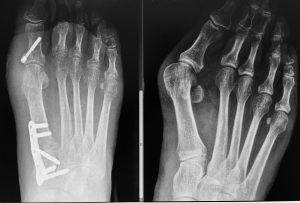

🔹 Osteotomías correctivas: se realizan cortes controlados en el hueso para corregir su alineación y fijarlos con placas o clavos.

🔹 Cirugía guiada por imagen: mayor precisión, menor invasión y mejor planificación.

Cada caso es valorado por nuestro equipo de traumatología y cirugía ortopédica, que realiza un estudio radiológico completo y planifica el tratamiento más adecuado según la edad, la localización de la deformidad y el estado general del paciente. Contamos con experiencia en cirugía infantil y de adultos, así como en técnicas de corrección progresiva y procedimientos reconstructivos complejos.